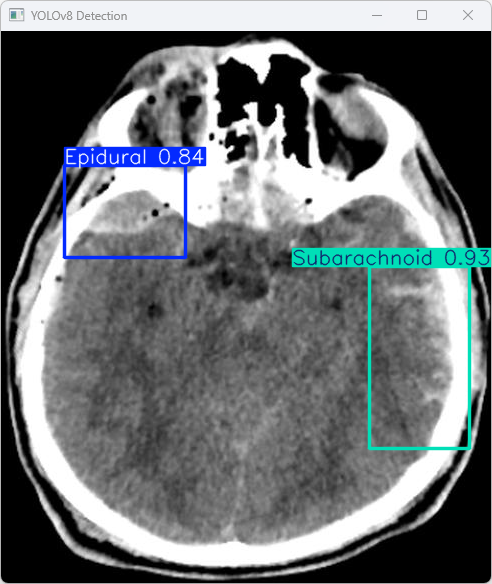

执行imgTest.py代码后,会将执行的结果直接标注在图片上,结果如下:

这段输出是基于YOLOv8模型对图片“imagetest.jpg”进行检测的结果,具体内容如下:

图像信息:

(1)处理的图像路径为:TestFiles/imagetest.jpg。

(2)图像尺寸为640×576像素。

检测结果:

(1)模型在图片中检测到:1 个 Epidural(硬膜外)、1 个 Subarachnoid(蛛网膜下腔)。

处理速度:

(1)预处理时间: 5.0 毫秒

(2)推理时间: 41.8 毫秒

(3)后处理时间: 64.9毫秒

总结:

YOLOv8模型成功检测了图像中的两个类别,说明模型在这些类别上的表现可靠。